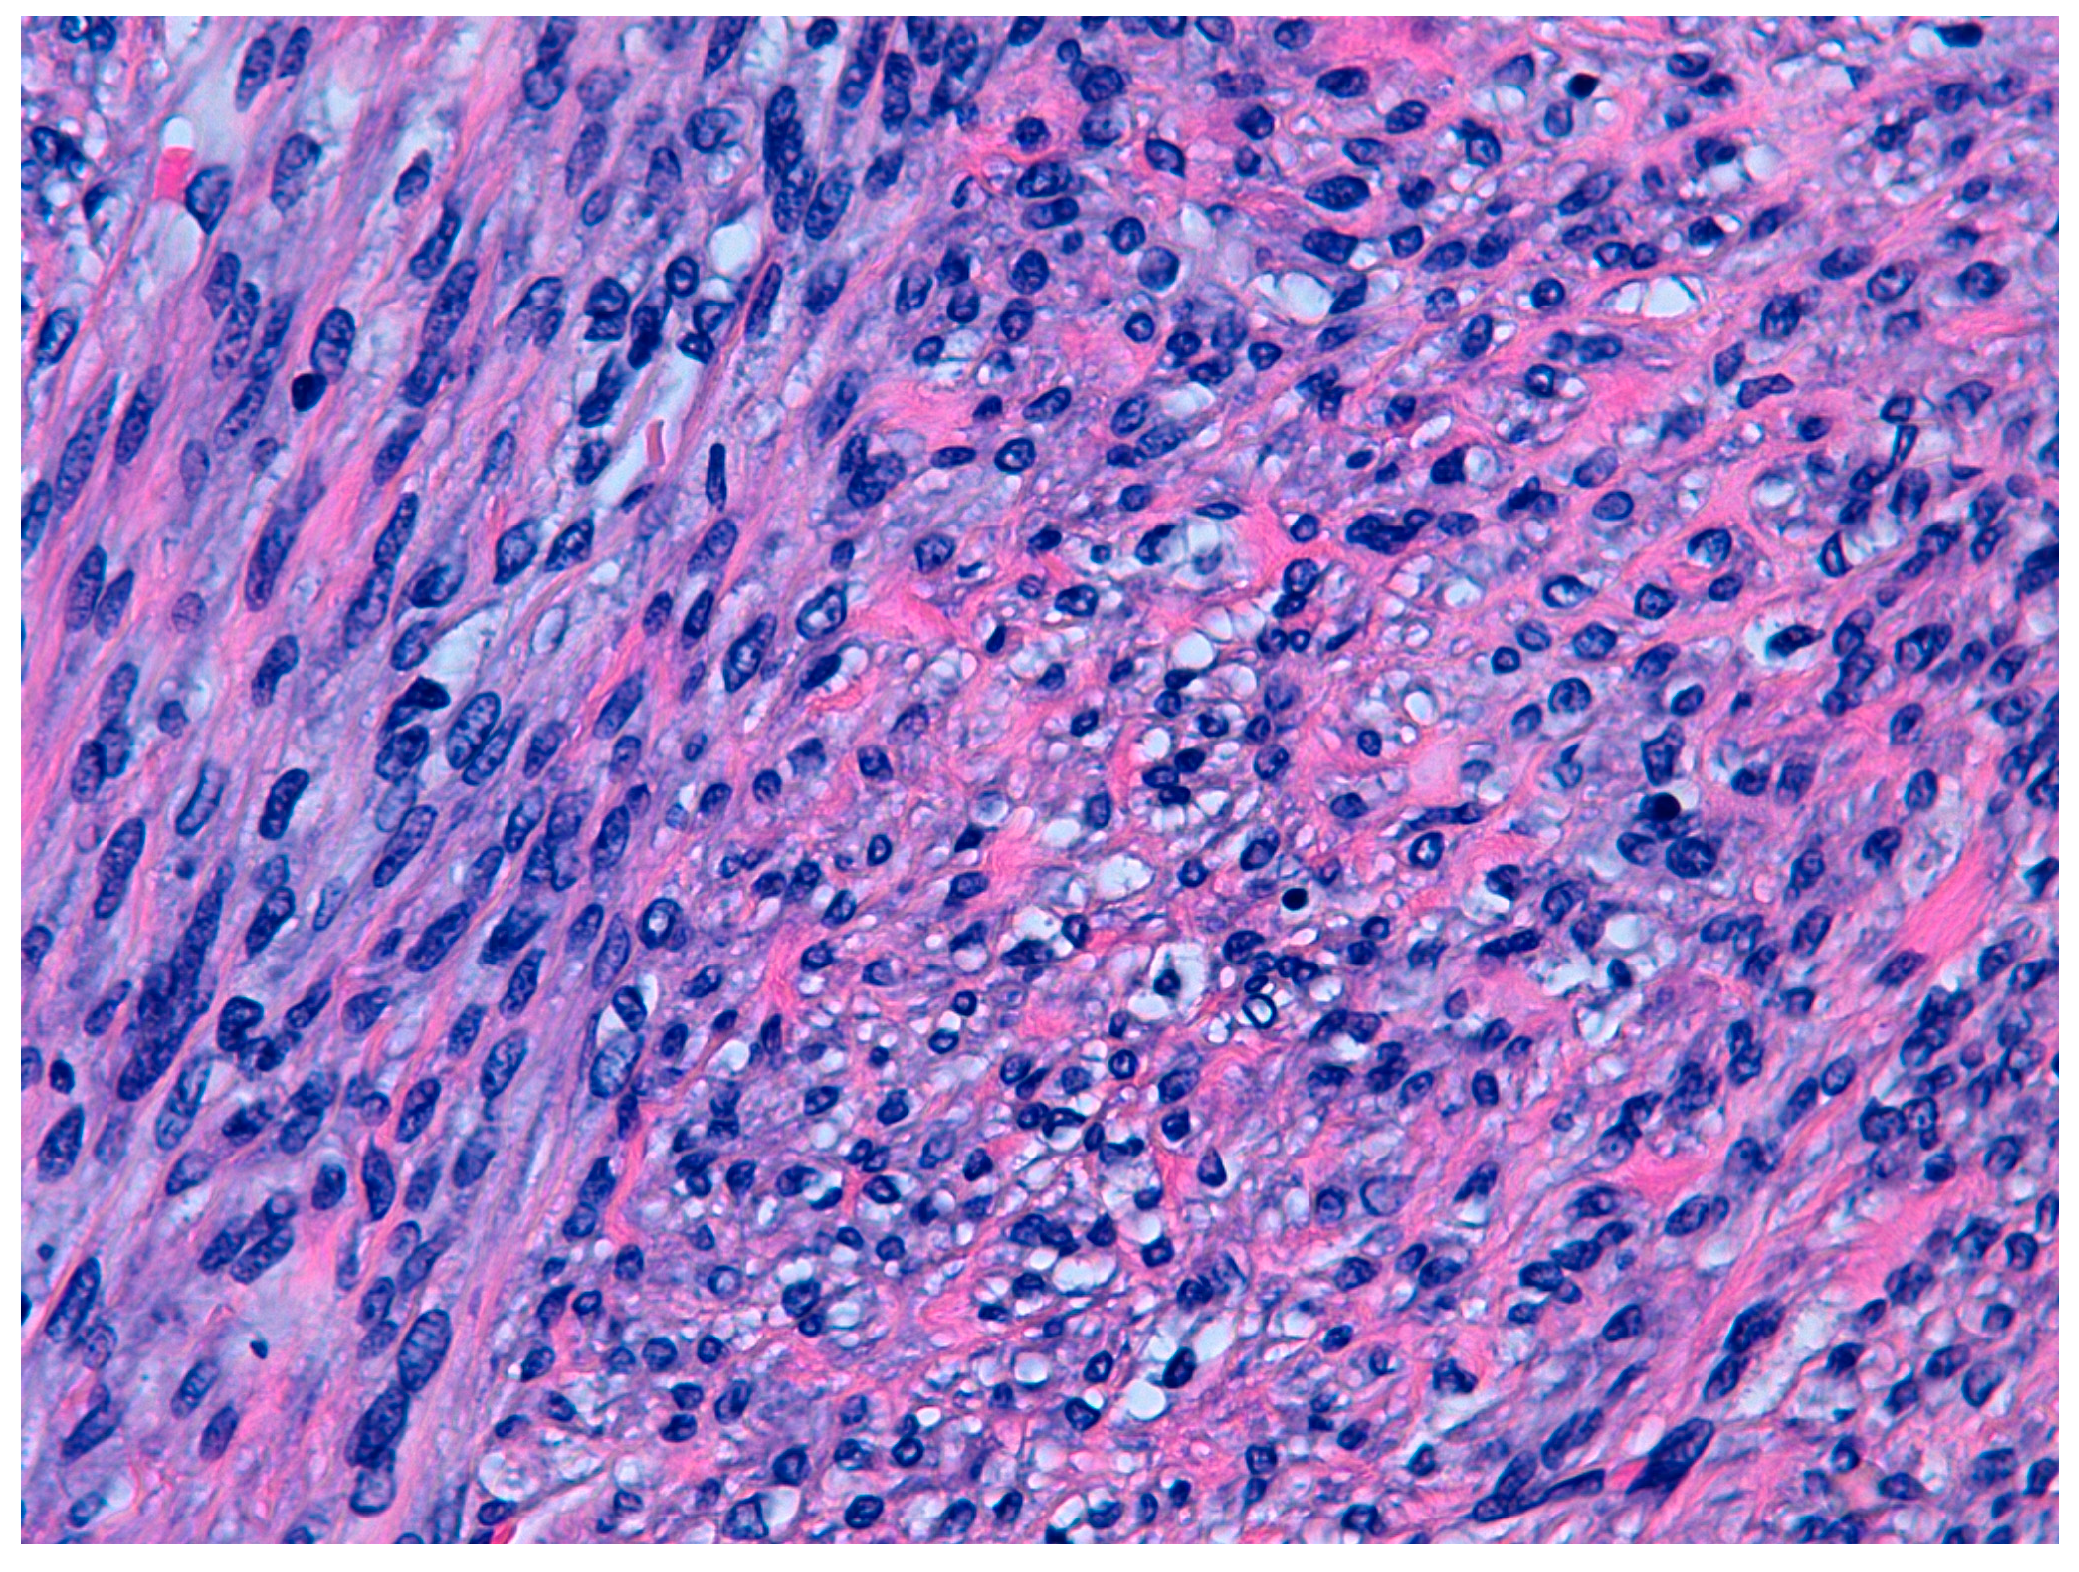

According to the 2014 WHO criteria [9], the pathological diagnosis of STUMP is based on the presence of coagulative necrosis (cases 1 and 4), the finding of 24 mitoses per field and moderate focal atypia (case 2), and diffuse moderate atypia (case 3) (Figure 1 and Figure 2).

Figure 1.

Hematoxilin and eosin staining (10×). Focal cell necrosis. Case 1.